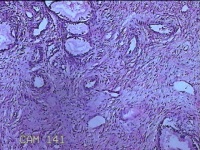

性别

女

年龄

44岁

临床诊断

宫颈赘生物

一般病史

发现宫颈赘生物2年余。

标本名称

宫颈组织

大体所见

灰白暗红色组织3.8x1.5x0.8cm一块,表面光滑,以宫颈12点缝线标记处切开,切面灰白粉红色,质软,宫颈3点处见灰白粉红色囊性肿物1.8x1.5x0.3cm一个,切开肿物,内见大量乳白色内容物,囊壁厚0.1cm。